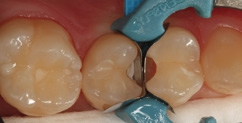

Die Zähne 24 und 25 des 51-jährigen Tierarztes wiesen diskrete, aber behandlungsbedürftige Approximalläsionen auf – gut erkennbar an der Transluzenzänderung der Randleisten in Abbildung 16. Die Abbildung 17 zeigt die exkavierten und mit FACE-Light-Kontrolle [6] als kariesfrei eingestuften Kavitäten, bereits mit Teilmatrizen und einem Spannring (Palodent V3, Dentsply Sirona) isoliert. Bei Verwendung dünner Teilmatrizen können durchaus zwei benachbarte Kavitäten gleichzeitig versorgt werden. Die noch vorhandene Schmelzlamelle zu dem Goldinlay an Zahn 25 berechtigt den Verbleib des klinisch ansonsten intakten Goldinlays. Die Abbildung 18 zeigt die Situation nach der adhäsiven Versiegelung mit einem Universaladhäsiv (Prime&Bond active, Dentsply Sirona) nach vorangegangener Schmelzätzung, die Abbildung 19 die ausgearbeiteten und polierten minimalinvasiven Slot-Füllungen – ausschließlich aus SDR flow+ in der Farbe A2. Die Polymerisation erfolgte für 40 Sekunden aus okklusaler Richtung, gefolgt von einem weiteren Polymerisationszyklus von 20 Sekunden über die bukkale Flanke. Durch die gewählte Versorgungsform ist mit Sicherheit die am wenigsten invasive und auch die für den Patienten wirtschaftlichste Versorgungsvariante gewählt worden, da ein Austausch des Goldinlays vermeidbar war.

Fall 5 Minimalinvasive Slot-Versorgung an Zähnen 13 und 14

Die Zähne 13 und 14 des 19-jährigen Patienten zeigten aktive Primärläsionen, die Anzeichen der hohen Kariesaktivität des jungen Patienten waren (Abb. 20). Beide Kavitäten wurden mit dem Komet Mikropräparationsinstrument 8830M.314012 präpariert und die approximalen Flanken mithilfe eines diamantierten, wabenförmigen Feinkornfinierstreifens WS 25F (Komet Dental) geglättet. Die Abbildung 21 zeigt die beiden präparierten Kavitäten mit bereits angelegten Palodent V3-Spannringen und Teilmatrizenfolien. Der distal gelegene Spannring wurde von seinem Ringdurchmesser nach distal orientiert, um eine bessere Zugänglichkeit zu den beiden Kavitäten zu gewährleisten. Gerade im Prämolarenbereich ist dieses Vorgehen oftmals sehr hilfreich. Die Abbildung 22 zeigt die fertige Versorgung mit SDR flow+ in der Farbe A2 nach adhäsiver Vorbehandlung mit Prime&Bond active nach Schmelzkonditionierung mit Phosphorsäuregel. Generell ist bei den Universaladhäsiven der selbstkonditionierenden Vorbehandlung des Dentins der Vorzug zu geben. Eine selektive Schmelzätzung bei so schmalen und kleinen Kavitäten ist aber nicht so einfach umzusetzen. Ein Pluspunkt bei allen Universaladhäsiven ist deren Toleranz auf eine vorangegangene Ätzung des Dentins mit Phosphorsäuregel: Diese „Etch&Rinse“-Anwendung hat keinen negativen Einfluss auf die Randintegration und die Haftung. Eine Metaanalyse zu Universaladhäsiven attestiert den milden Universaladhäsiven sehr gute Haftwerte auf Dentin im selbstkonditionierenden Modus [48]. Eine zusätzliche Phosphorsäurekonditionierung ergibt hier keine Vorteile, da die Dentin-Haftwerte sich im selbstkonditionierenden und „Etch&Rinse“- Modus nicht unterscheiden [10,56], aber auch keine Nachteile. Auch dieses Beispiel zeigt die gute Farbadaptation und Randintegration des Bulk-Flow-Komposits.